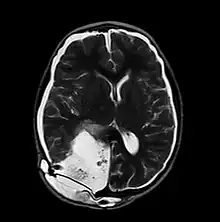

| MRI of Pseudomeningocele in 8 years old male patient | |